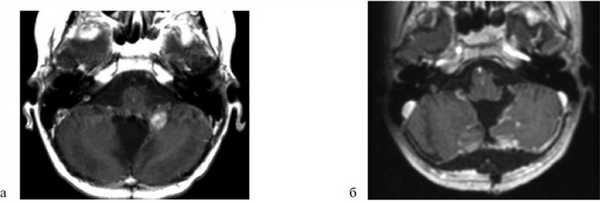

Пациент А., 14 лет. Госпитализирован 16.06.15. Диагноз: медуллобластома червя и левой гемисферы мозжечка. Состояние после субтотального удаления опухоли 17.05.10, установки резервуара Оммайя, ЛТ и ПХТ. Рецидив опухоли (рис. 1, а). Рис. 1. Наблюдение 1: пациент А. а — МРТ до операции (режим T1 с контрастом); б — МРТ через 1,5 мес после операции (режим T1 с контрастом). Пояснения в тексте.

В неврологическом статусе при поступлении: мозжечковая симптоматика (шаткость в позе Ромберга, без сторонности, пальценосовую пробу выполняет правильно с выраженной интенцией, походка атактическая).

16.06.15 выполнена операция: удаление рецидивной медуллобластомы в области средней ножки мозжечка (GTR). После операции в течение ночи ребенок наблюдался в реанимации. В неврологическом статусе отрицательной динамики не наблюдалось. Дыхание самостоятельное, через естественные дыхательные пути. Питание самостоятельное. На 6-е сутки выписан. Через 1,5 мес после удаления опухоли выполнена контрольная МРТ головного мозга: признаков остатка опухоли нет (см. рис. 1, б).

Пациентка Б., 4 года. Госпитализирована 12.05.15. Диагноз: анапластическая эпендимома IV желудочка. Состояние после удаления опухоли 18.07.12. Вентрикулоперитонеальное шунтирование 06.08.13. Состояние после ПХТ и Л.Т. Рецидив опухоли (рис. 2, а). Рис. 2. Наблюдение 2: пациентка Б. а — МРТ до операции (режим T1 с контрастом); б — МРТ через 1 мес после операции (режим T1 с контрастом). Пояснения в тексте.

В неврологическом статусе при поступлении: мозжечковая симптоматика (шаткость в позе Ромберга, пальценосовая проба с легкой интенцией с двух сторон, походка атактическая).

12.05.15 выполнена операция: удаление парастволового узла рецидива эпендимомы ЗЧЯ справа с мониторингом вызванных моторных потенциалов (GTR).

После операции несколько часов наблюдалась в отделении реанимации. В неврологическом статусе отмечен легкий парез VI нерва справа, сохранялась мозжечковая симптоматика. На 6-е сутки девочка выписана из стационара. На МРТ через месяц признаков опухоли нет (см. рис. 2, б).